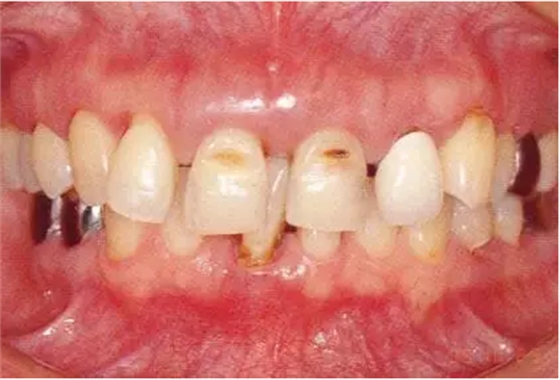

▲圖19-1

40歲,女性。來院主訴為牙齦出血,牙體晃動?;颊卟晃鼰?,因此沒有全身性問題。有明顯的牙周炎,發(fā)生了牙體移動,前牙區(qū)前突。下頜右側磨牙缺失,醫(yī)生認為有必要進行包括牙周修復、正畸治療、種植治療等在內的綜合性治療。

▲圖19-2,3

上下頜咬合面照。

▲圖19-4

X光片。牙槽骨明顯缺失。